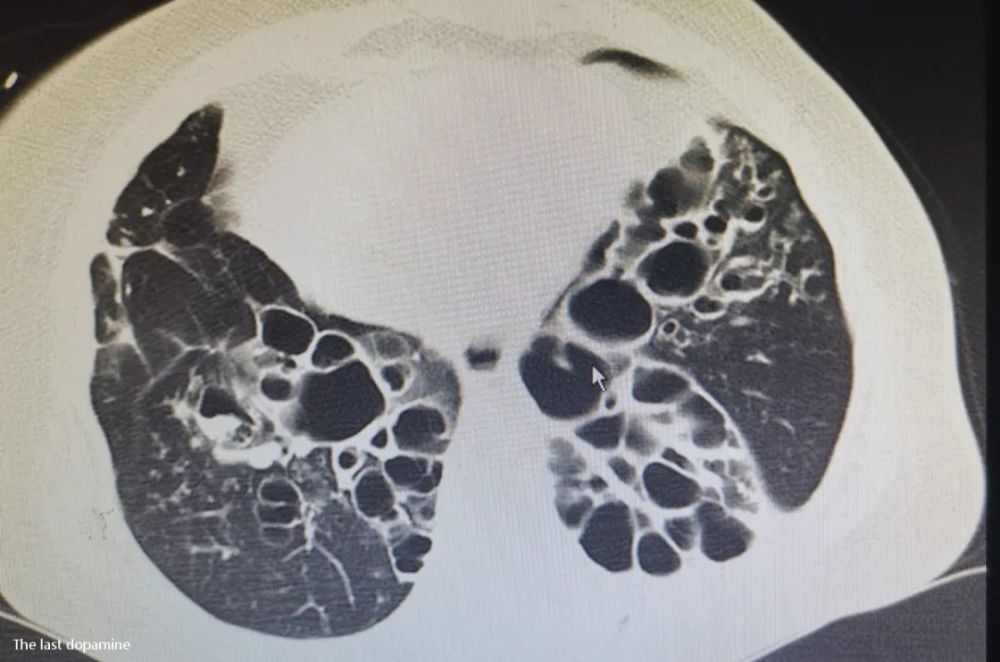

看着电脑屏幕上的胸部CT片子 , 我突然有一种错觉:这分明是一双蝴蝶的翅膀 , 哪里是病人的两肺 。

我又翻看了病人的检查资料 , 尤其是胸部CT让我印象深刻 , 因为我甚至有一种错觉:眼前的图片分明是一双蝴蝶的翅膀 , 那里是病人的两肺 。

眼前他无动于衷 , 我只好再次用最通俗的话来补充:“她的肺几乎已经毁损 , 两个肺的功能不如别人半个肺 。 你现在看着是一口口的咯血 , 严重的情况会一碗碗的咯血 , 病人也会因为休克、窒息等情况短时间内死亡 。 如果真的出现了这么严重的情况 , 你能不能接受结果?”

在宣布临床死亡的那一刻 , 我竟再次想到了她那像极了蝴蝶翅膀的两肺 , 又想起了那句“我也对得起她了” 。